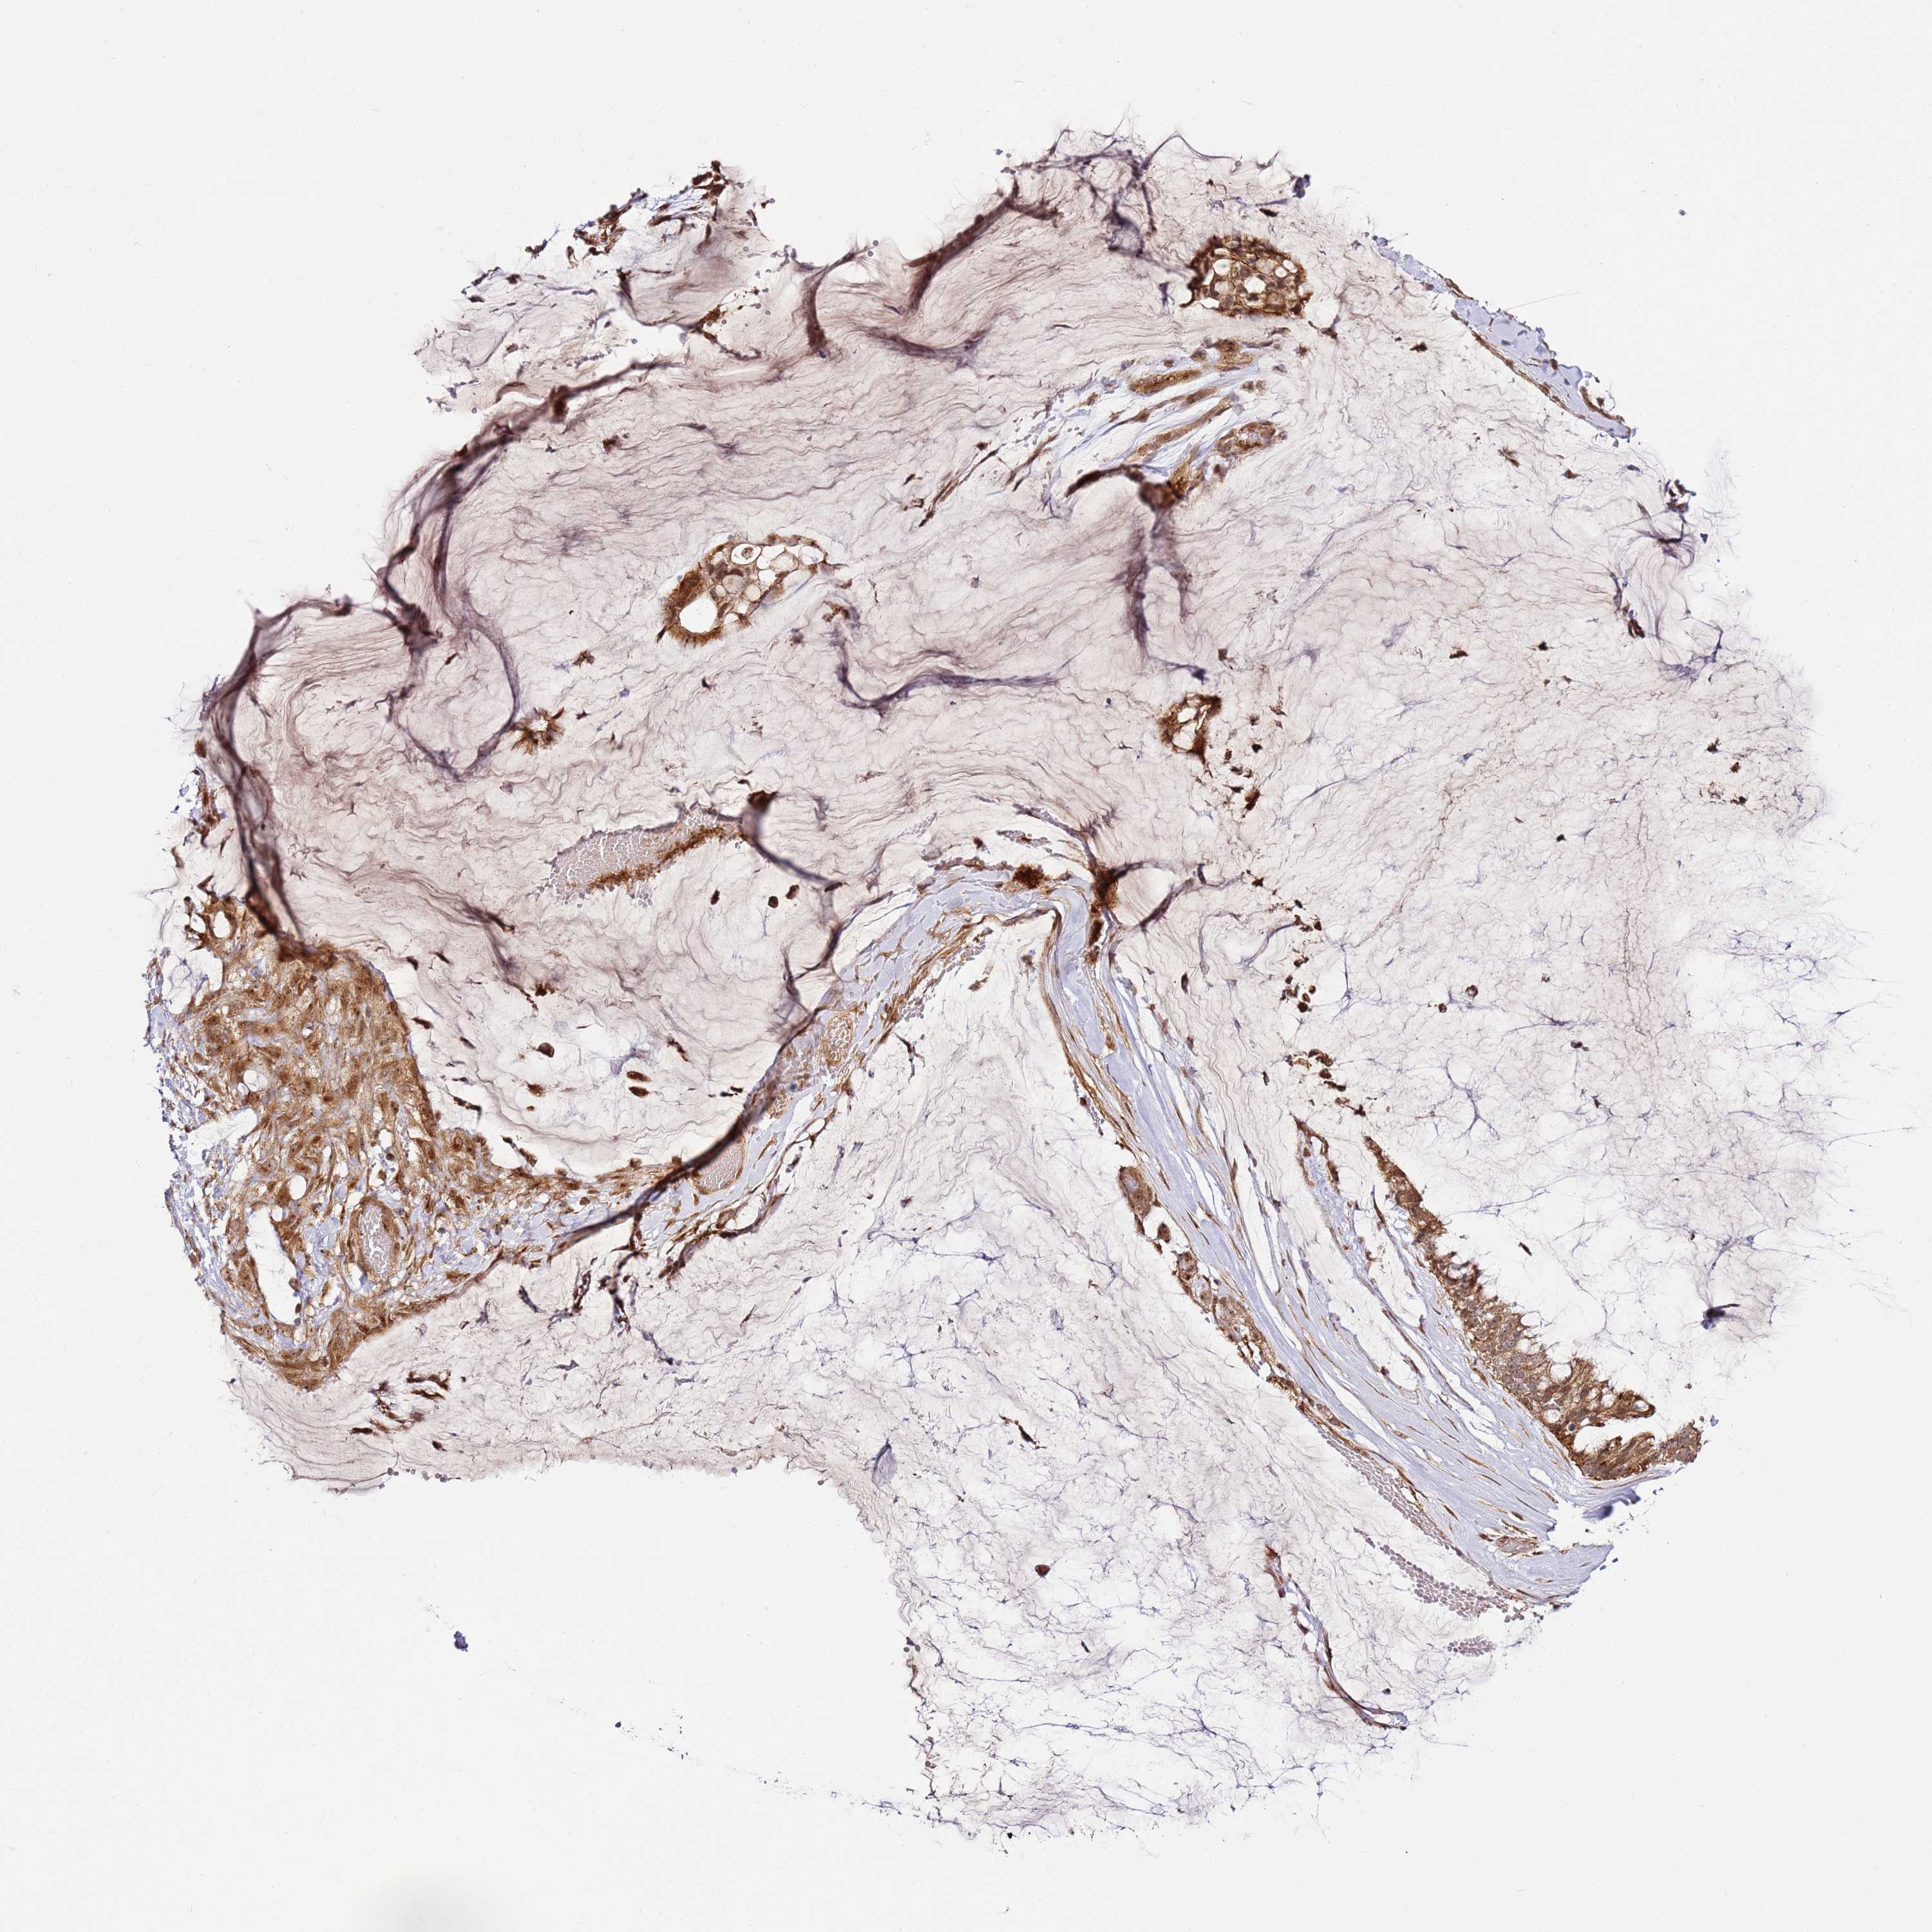

OVARIAN CANCER - Protein expressioni

A mouse-over function shows sample information and annotation data. Click on an image to view it in a full screen mode. Samples can be filtered based on level of antibody staining by selecting one or several of the following categories: high, medium, low and not detected. The assay and annotation is described here.

Note that samples used for immunohistochemistry by the Human Protein Atlas do not correspond to samples in the TCGA dataset.

Antibody stainingi

Antibody staining in the annotated cell types in the current human tissue is reported as not detected, low, medium, or high, based on conventional immunohistochemistry profiling in selected tissues. This score is based on the combination of the staining intensity and fraction of stained cells.

Each image is clickable and will lead to virtual microscopy that enables deeper exploration of all samples and also displays staining intensity scores, fraction scores and subcellular localization as well as patient and tissue information for each sample.

Antibody HPA046759

Staining

High

Medium

Low

Not detected

Intensity

Strong

Moderate

Weak

Negative

Quantity

>75%

75%-25%

<25%

None

Location

Nuclear

Cytoplasmic/membranous

Cytoplasmic/membranous,nuclear

Cystadenocarcinoma, serous, NOS

Carcinoma, endometroid

Cystadenocarcinoma, mucinous, NOS

Carcinoma, NOS